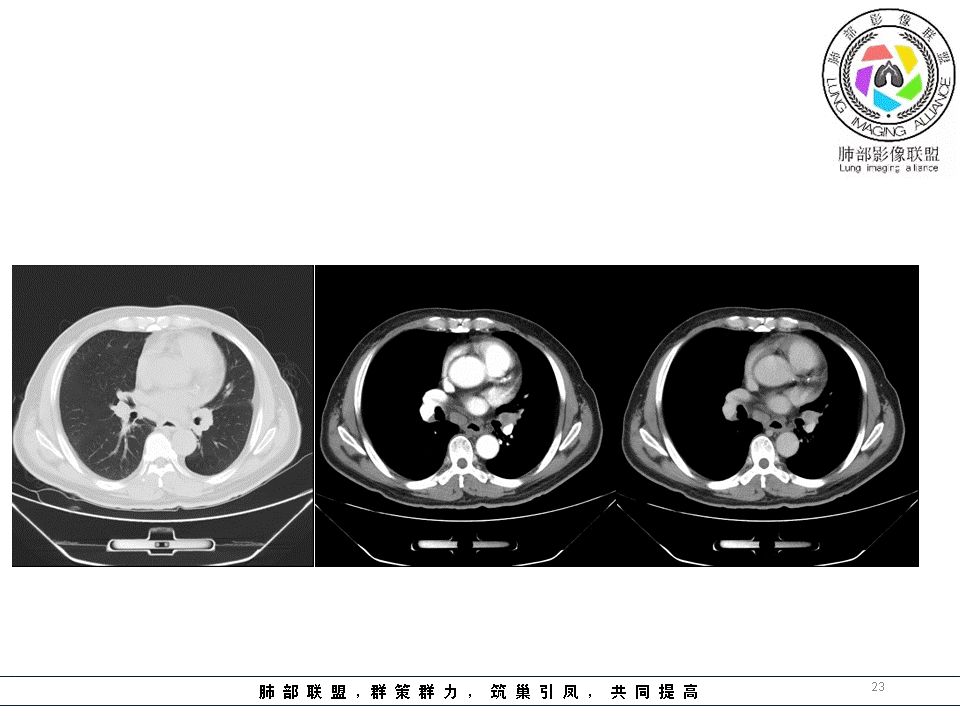

南边:但是我们看纵隔就多发的肿大淋巴结,部分融合成团。

南边:而且这些淋巴结,有些直接主要是压迫支气管壁,但是有些是突入到支气管腔内的。可惜我截的图发不上来。就左上舌段,支气管壁明显的增厚。有些明显腔内突的一个结节的,但是远的没有阻塞的特点。南边:增强以后呢,这个病灶明显强化,部分的似乎有环形强化的迹象,但不是很典型。

我们看这个主支气管的层面,主支气管明显受压,有变形的,但是软骨是没有突破的。

但是有一个地方有问题的,左侧的上叶的下舌段这个区域:

左上叶舌段这个气管腔内是有东西凸进去。

结果:肺腺癌并纵膈淋巴结转移